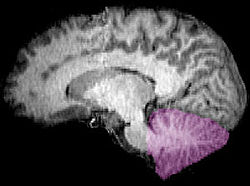

Cerebellum NIH.png

Figure 1a: A human brain, with the cerebellum in purple.